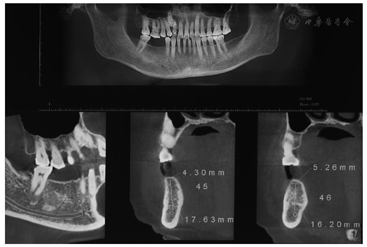

面照;B:颊面照CBCT检查:45牙缺牙区牙槽嵴顶宽度4.30 mm,高度17.63 mm;46牙缺牙区牙槽嵴顶宽度5.26 mm,高度16.20 mm(图2)。